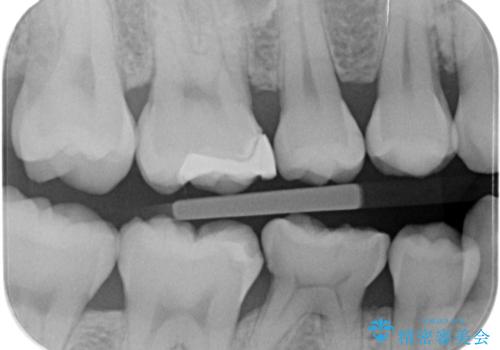

- 歯が染みるとの事で来院。

レントゲンを撮影したところ虫歯がありましたので拡大鏡下で虫歯を取り除いた後、e-maxインレーにて治療を行いました。

適合の良い詰め物が入りました。